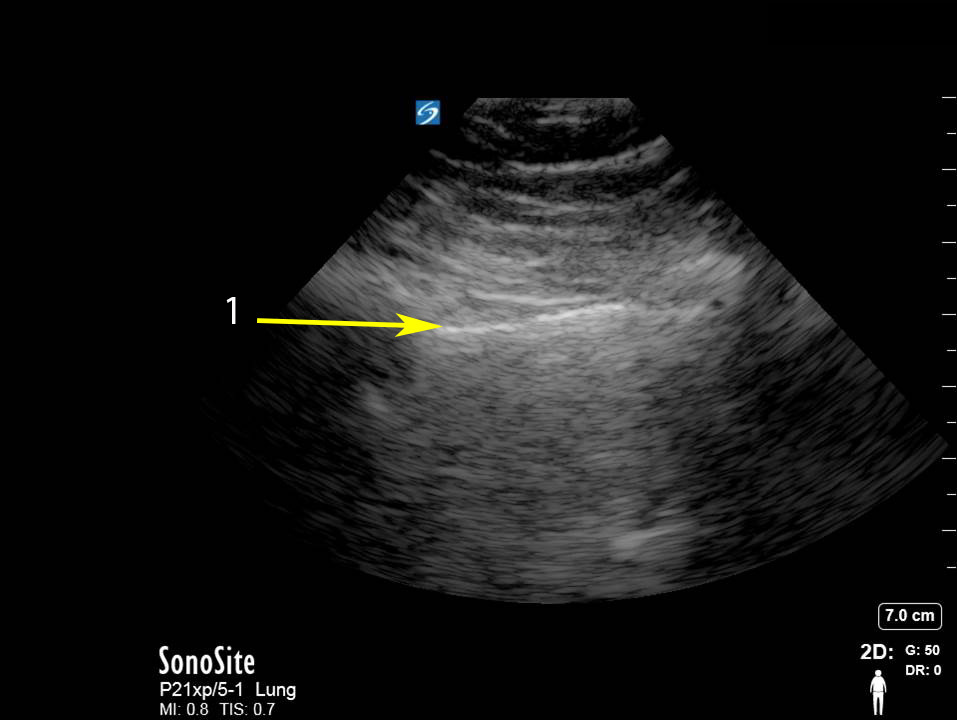

Bild: Lunge, Bewertung der Pleura, Lungenverschiebung

Pleuralinie